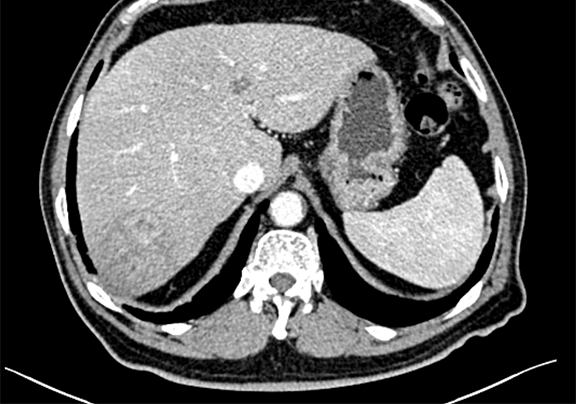

术前CT检查:动脉期

静脉期

现病史:患者9天前无明显诱因查体发现肝内占位性病变,右侧肋缘下轻度触痛,无区域放射,尚可耐受,与体位、活动无关,偶发间断性头晕、头痛,自诉50余年胆囊结石病史,无予以特殊治疗及药物服用,无恶心、呕吐,无腹痛、腹胀,无右侧肩部放射痛,无胸闷、胸痛,无咳嗽、咳痰,无睡眠障碍,小便轻度尿刺痛感,饮食正常,2016-05-23于我院行健康查体显示:肝脏体积正常,肝内呈细密点状回声,欠均匀,探及一枚等低回声结节,大小约6.0cm ×5.0cm 呈椭圆形,内部回声较均匀,胆囊大小形态正常,毛糙,内见一乳头样高回声,大小约0.7cm ×0.6cm 不随体位移动,后方无声影,囊腔内可见强回声,呈泥沙样及胆泥样,范围约4.2cm× 1.9cm 后伴声影,随体位改变移动。脂肪肝(轻度)肝内结节 考虑血管瘤,建议CT随访,胆囊息肉,胆囊炎并胆囊结石,患者自发病以来未予以特殊治疗及用药。

辅助检查: 肝右叶肿块,肝Ca?